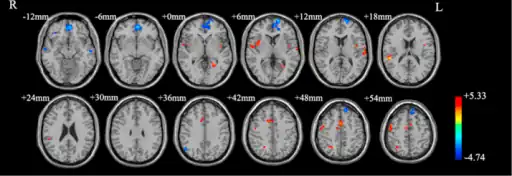

Functional neuroimaging during symptom provocation has observed abnormal activity in the orbitofrontal cortex, left dorsolateral prefrontal cortex, right premotor cortex, left superior temporal gyrus, globus pallidus externus, hippocampus and right uncus. Weaker foci of abnormal activity were found in the left caudate, posterior cingulate cortex and superior parietal lobule.[61] However, an older meta analysis of functional neuroimaging in OCD reported the only consistent functional neuroimaging findings have been increased activity in the orbital gyrus and head of the caudate nucleus, while ACC activation abnormalities were too inconsistent.[62] A meta analysis comparing affective and non affective tasks observed differences with controls in regions implicated in salience, habit, goal-directed behavior, self-referential thinking and cognitive control. For non affective tasks, hyperactivity was observed in the insula, ACC, and head of the caudate/putamen, while hypoactivity was observed in the medial prefrontal cortex (mPFC) and posterior caudate. Affective tasks were observed to relate to increased activation in the precuneus and posterior cingulate cortex(PCC), while decreased activation was found in the pallidum, ventral anterior thalamus and posterior caudate.[63] The involvement of the cortico-striato-thalamo-cortical loop in OCD as well as the high rates of comorbidity between OCD and ADHD have led some to draw a link in their mechanism. Observed similarities include dysfunction of the anterior cingulate cortex, and prefrontal cortex, as well as shared deficits in executive functions.[64] The involvement of the orbitofrontal cortex and dorsolateral prefrontal cortex in OCD is shared with bipolar disorder and may explain their high degree of comorbidity.[65] Decreased volumes of the dorsolateral prefrontal cortex related to executive function has also been observed in OCD.[66]

People with OCD evince increased grey matter volumes in bilateral lenticular nuclei, extending to the caudate nuclei, with decreased grey matter volumes in bilateral dorsal medial frontal/anterior cingulate gyri.[67][68] These findings contrast with those in people with other anxiety disorders, who evince decreased (rather than increased) grey matter volumes in bilateral lenticular / caudate nuclei, as well as decreased grey matter volumes in bilateral dorsal medial frontal/anterior cingulate gyri.[68] Increased white matter volume and decreased fractional anisotropy in anterior midline tracts has been observed in OCD, possibly indicating increased fiber crossings.[69]

Brain regions showing different functional connectivity between obsessive–compulsive disorders and controls

Some parts of the brain showing abnormal activity in OCD